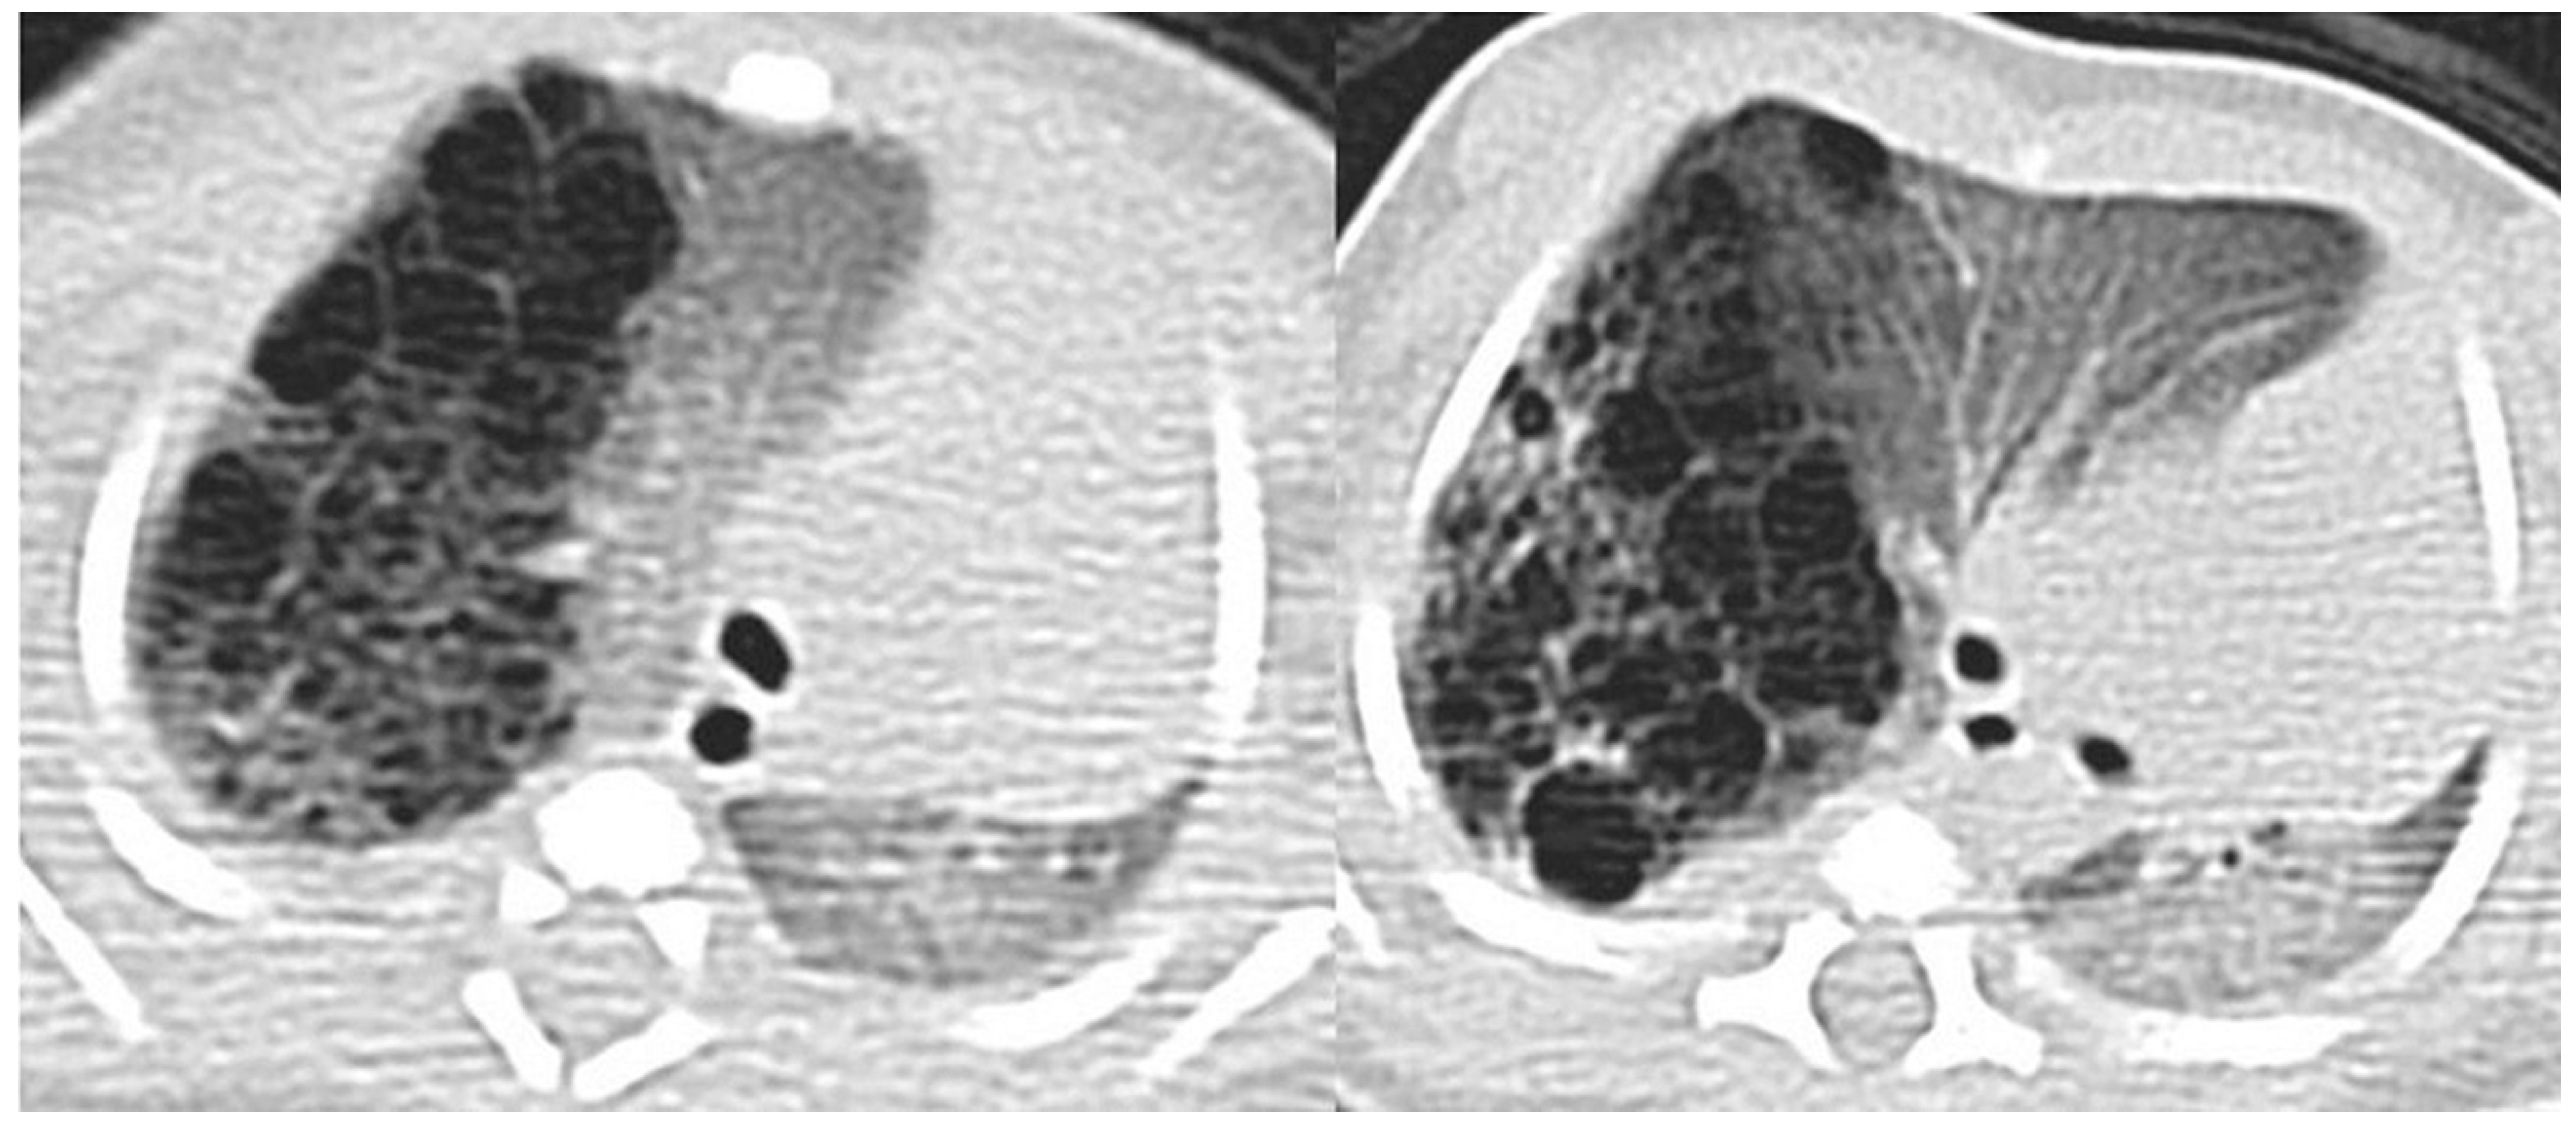

3.4.2. Congenital Pulmonary Airway Malformations

| Imaging | acinar dysgenesis or dysplasia; cardiovascular anomalies | large cystic lesions (2–10 cm) with small cysts around | multiple small cysts (0.5–2 cm). cardiovascular and renal malformation may be associated | “adenomatoid”: small cystic lesions (<5 mm) with solid aspect | large multilocular cysts (>10 cm) at the lobe’s periphery |